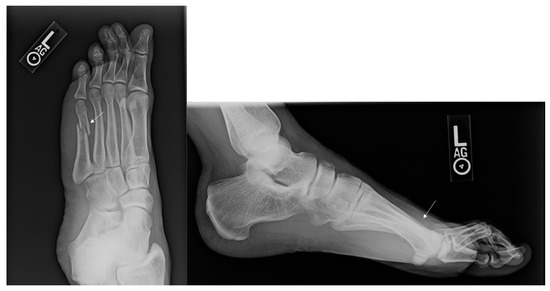

Figure 1.

Injury Films for Displaced Metatarsal Fractures from a Gunshot. Displayed above are the injury radiographs for second and third metatarsal fractures following a gunshot injury. The arrows above identify the metatarsal fractures.